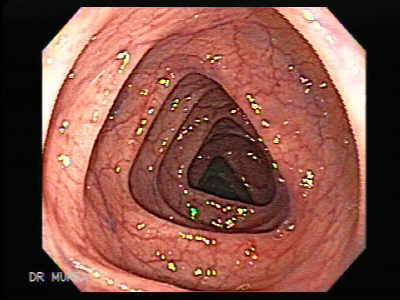

Kolonoskopi, kalın barsağın tamamının ve gerektiğinde ince barsağın son kısmının yumuşak,bükülebilir 8-9mm kalınlığında kameralı bir aletle incelenmesidir.Tanı değeri %95'lerin üzerindedir.

Günümüz teknolojisinde bu işlem ,hem barsak hastalıklarının tanısında (gerektiğinde ağrı duyulmadan parça alınması) ,hem de tedavisinde (poliplerin ameliyatsız alınması vb.) en iyi yöntemdir